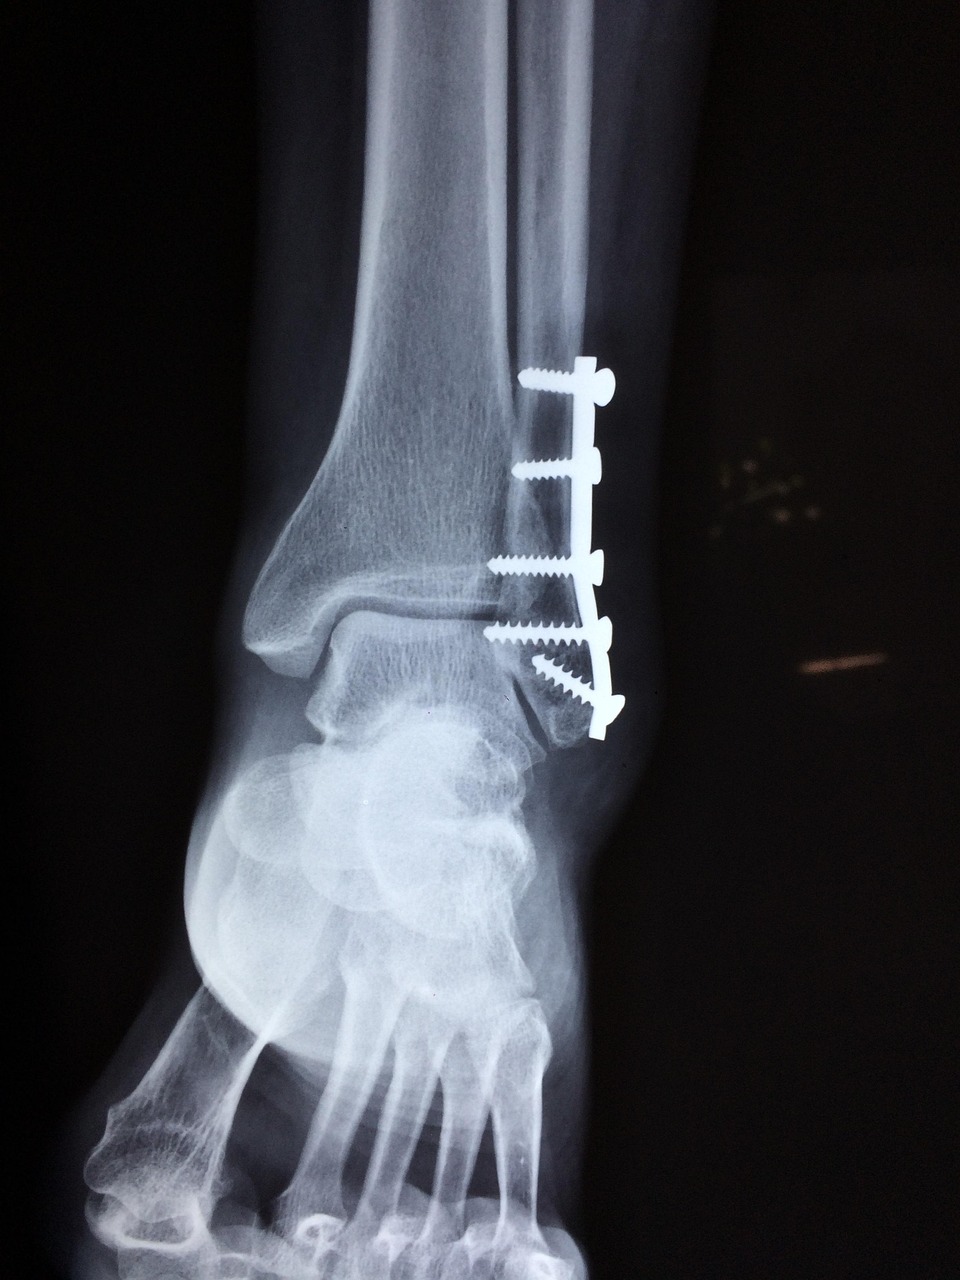

- Reabilitação Pós-Operatória de Cirurgia Ortopédica

Após uma cirurgia ortopédica, a reabilitação adequada é essencial para restaurar a mobilidade, reduzir a dor e recuperar a funcionalidade. Na TIBIA, acompanhamos o processo de recuperação de forma individualizada, respeitando as fases da cicatrização e os protocolos clínicos indicados. Intervimos em casos de próteses articulares, artroscopias, fraturas, reparações ligamentares e outras cirurgias, com foco na mobilização progressiva, no reforço muscular e na retoma gradual das atividades do dia a dia — com segurança, eficiência e rigor clínico.